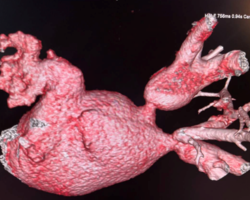

Пациент М., 54 лет наблюдался с длительной историей нарушений ритма сердца. Ранее ему была выполнена криоабляция, а спустя два года — радиочастотная абляция. Через два месяца после РЧА у пациента появились выраженная слабость и одышка при физической нагрузке. При дообследовании выявлены окклюзии левой верхней и левой нижней легочных вен.

С учётом тяжести состояния и высокого риска дальнейшего прогрессирования заболевания было принято решение о проведении эндоваскулярного восстановления проходимости легочных вен. Стентирование одновременно двух легочных вен является технически крайне сложным вмешательством и требует высокой экспертной подготовки. Подобные операции выполняются в ограниченном числе специализированных центров и НМИЦ кардиологии им. ак. Е.И. Чазова Минздрава России располагает наибольшим в стране опытом лечения данной категории пациентов.

Вмешательство проводилось через бедренный венозный доступ под местной анестезией. Основная сложность операции заключалась в полной окклюзии обеих легочных вен и необходимости точной навигации инструментов в условиях ограниченной визуализации. После реканализации поражённых участков были имплантированы стенты, обеспечившие надёжное восстановление просвета сосудов и полноценный венозный отток из лёгких.